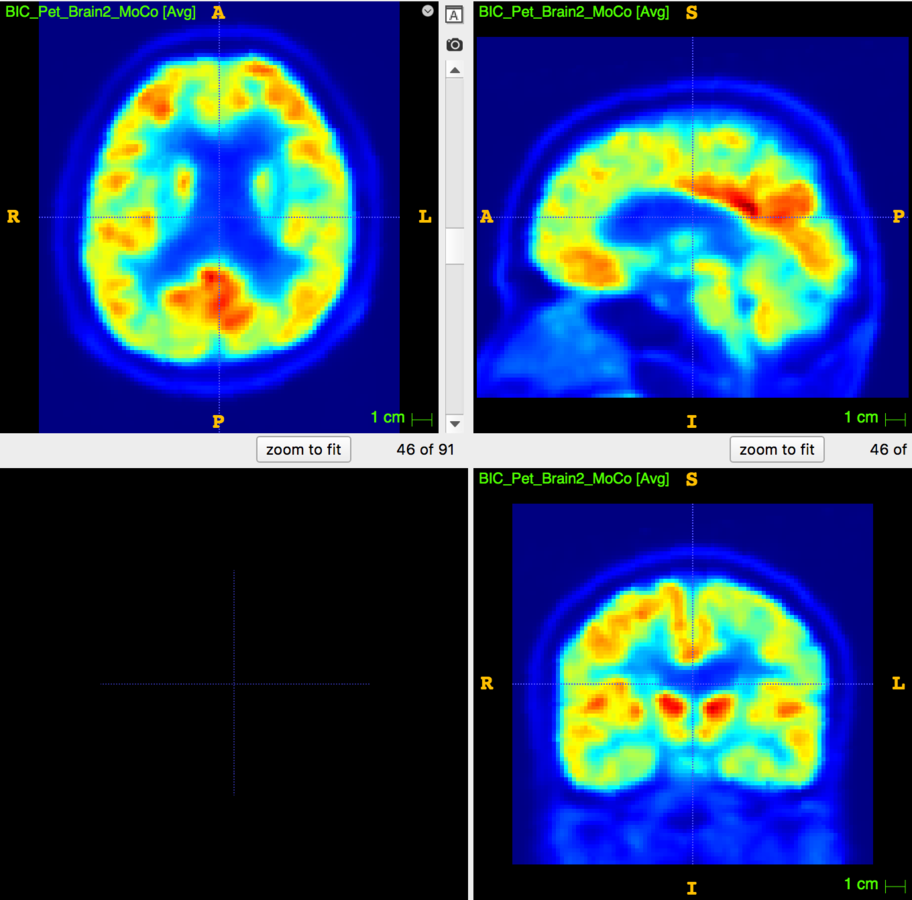

3D multimodal image resampling.

from

-

D. Poggiali, D. Cecchin, C. Campi, S. De Marchi, Oversampling errors in multimodal medical imaging are due to the Gibbs effect, Mathematics, doi:10.3390/math9121348

- D. Poggiali, D. Cecchin, S. De Marchi, Reducing the Gibbs effect in multimodal medical imaging by the Fake Nodes Approach, JCMDS, doi:10.1016/j.jcmds.2022.100040

High resolution "morphological" image

Segmentation mask

Low resolution "functional" image

Applications to medical imaging: